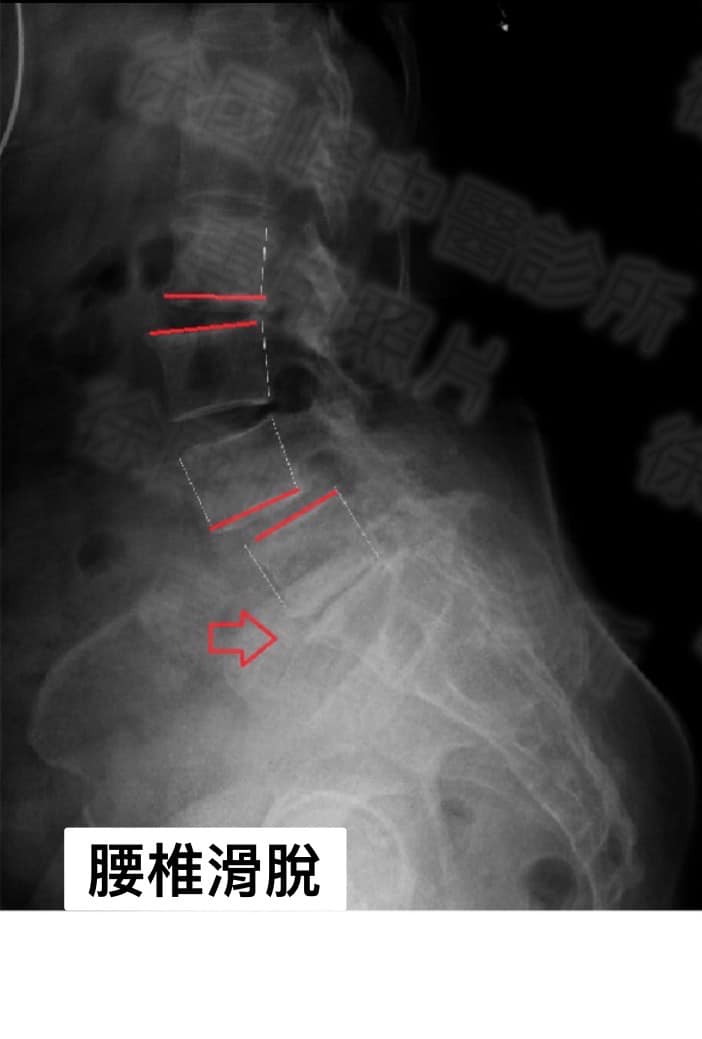

2.左側L4L5椎體滑脫